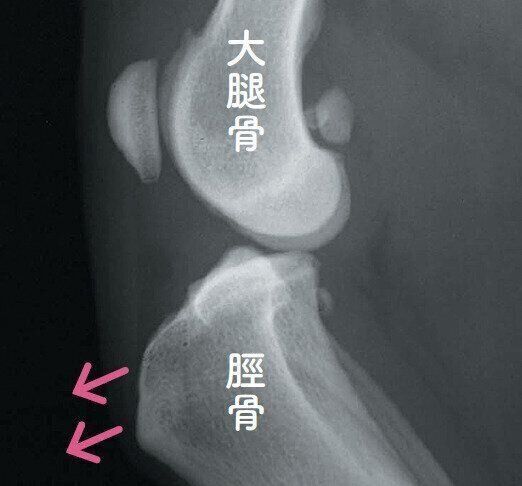

大腿骨頭壊死症の例

股関節にある大腿骨の先が壊死する病気で、小型犬に多く見られます。痛みを伴うため、写真のように足をかばいながらヒョコヒョコ歩くことがあります。